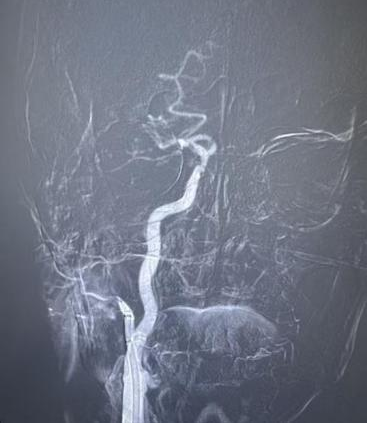

卒中中心神经内科介入团队再次临危受命。评估患者发病时间短、符合动脉取栓指征后,团队与介入导管室等科室无缝对接,争分夺秒开展手术。术中,王怀成副主任医师带领团队在复杂的血管解剖结构中精准导航,一次取栓便成功恢复了血管血流,手术圆满成功。